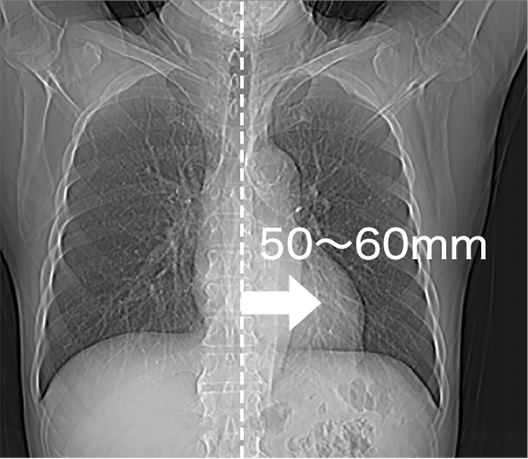

更輕鬆地定位待檢查區域

病床橫向最長可移動達 200 mm,即使在心臟或骨科(如肩部)等掃描部位,也能更容易將檢查區域置中,提高檢查效率

將心臟定位在視野中央附近

將四肢定位在視野中央附近